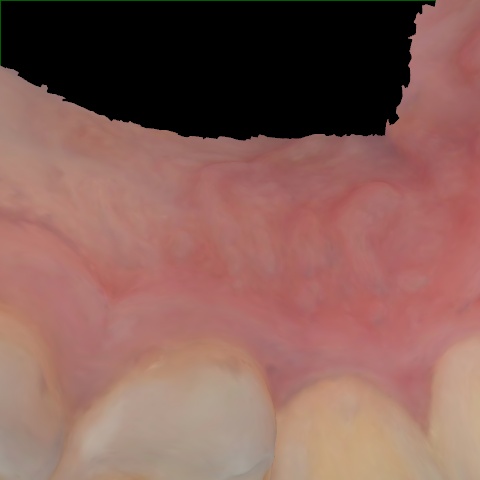

Annotated as "Good"